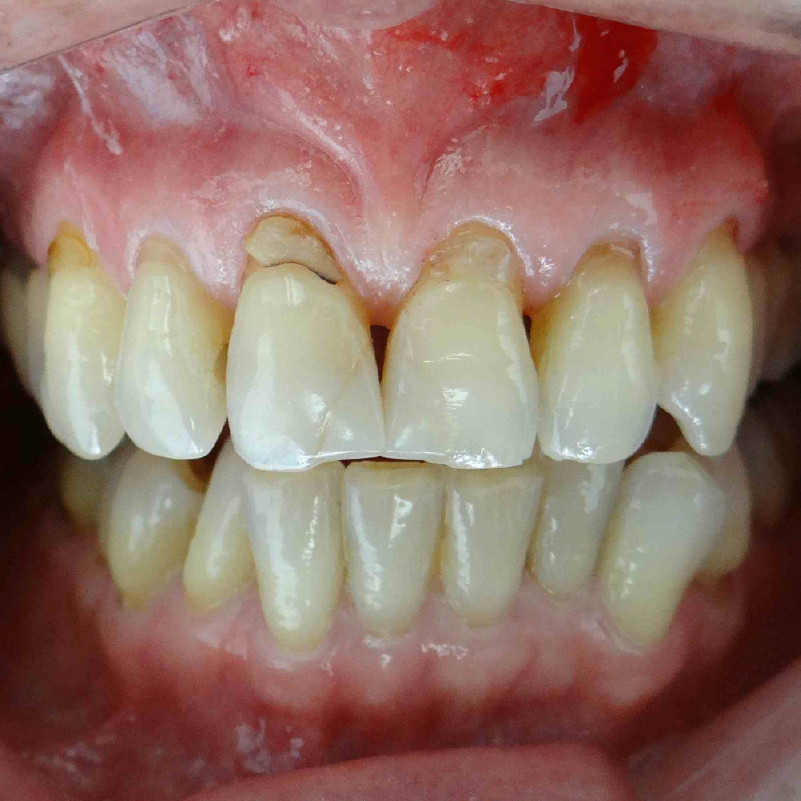

- Pacientes con gingivitis que presentan encías inflamadas, rojas y sangrantes durante el cepillado.

- Periodontitis en diferentes grados con pérdida de hueso alveolar y formación de bolsas periodontales profundas.

- Encías retraídas que exponen la raíz dental causando sensibilidad y problemas estéticos.